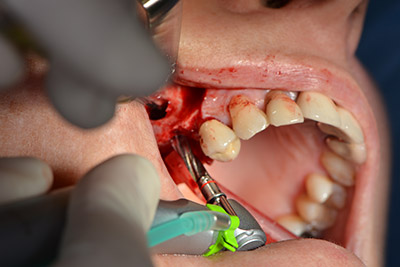

Procedura chirurgica per l'impianto

L'incisione classica (rilascio crestale e buccale) e la preparazione del lembo mucoperiosteo favoriscono un'ottima panoramica.

In questo caso vengono usati impianti di tipo SKY (bredent). Il loro protocollo chirurgico specifica una perforazione pilota di circa 1200 rpm (fig. 9).

Le vie indicate di seguito sono realizzate con una perforazione a velocità ridotta, pari a 300 rpm. In questa fase Implantmed dimostra la sua grande affidabilità. È possibile predefinire il protocollo chirurgico: per selezionare le varie posizioni, basta premere la lettera “P” con il controllo a pedale (da fig. 10 a 11).